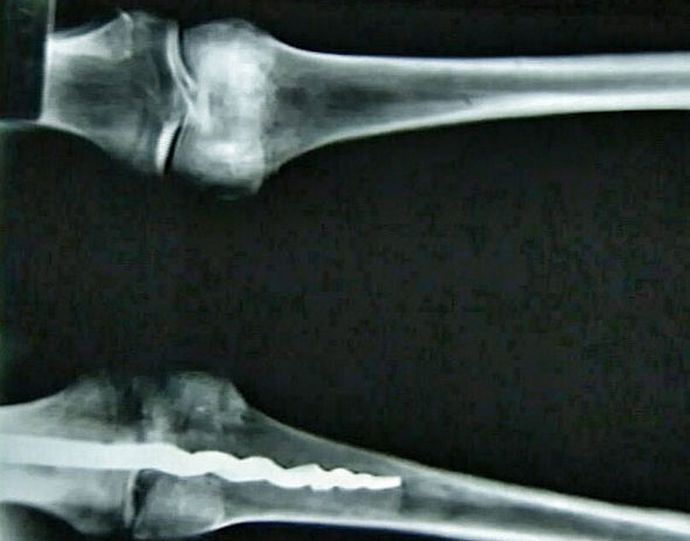

Fotografija odprtokodna skupina ameriških raziskovalcev DNK analiza egipčanske mumije je v njenem telesu našla resnično ortopedski zatič, ni slabši v oblikovanju sodobni kolegi. Edinstvena dolžina najdbe 23 centimeter, izdelana je iz kovine, njen dizajn pa je drugačen presenečenje ortopedskih zatičev, uporabljenih v medicine danes.

Po mnenju strokovnjakov so v kolenu moškega starodavni kirurgi dajte zatič, ki pritrdi kosti, in ga pritrdite organske smole. To so naredili tako spretno in strokovno, da najbolj zapletena operacija ni pustila sledi na bolnikovem telesu. Sodeč po ugotovljeni najdbi, metodah, uporabljajo ga zdravniki v sodobni medicini že dolgo znani našim prednikom in jih uspešno uporabljajo v praksi.

Še vedno ni znano, kdo točno je bil Egipčan, v kolenu ki je bil odkrit neverjeten zatič. Znanstveniki iz Američanov Univerza Brigham Young ga je videla povsem po naključju rentgenski žarki in nato odstranjeni iz telesa, nekoliko presenečeni njegovo odkritje.

Najdena mumija ni stara manj kot 3000 let, kar pomeni, da tudi takrat stari Egipčani so imeli potrebno znanje za sestavljanje zatiči, ki lahko pravilno popravijo razseljene kosti položaj in izvajanje kompleksnih kirurških operacij.

Znanstveniki še ne morejo razložiti narave skrivnostne najdbe, obrnili svoje ideje o starodavni medicini. Wilfred Griggs, vodilna raziskovalna skupina, v čigavih rokah se je izkazalo edinstvena mamica, prepričana, da nobenemu ne bo dal veliko natančno ugotovite, kako je uspelo ustvariti in umestiti egipčanske zdravnike moško telo je tako sodoben zatič.